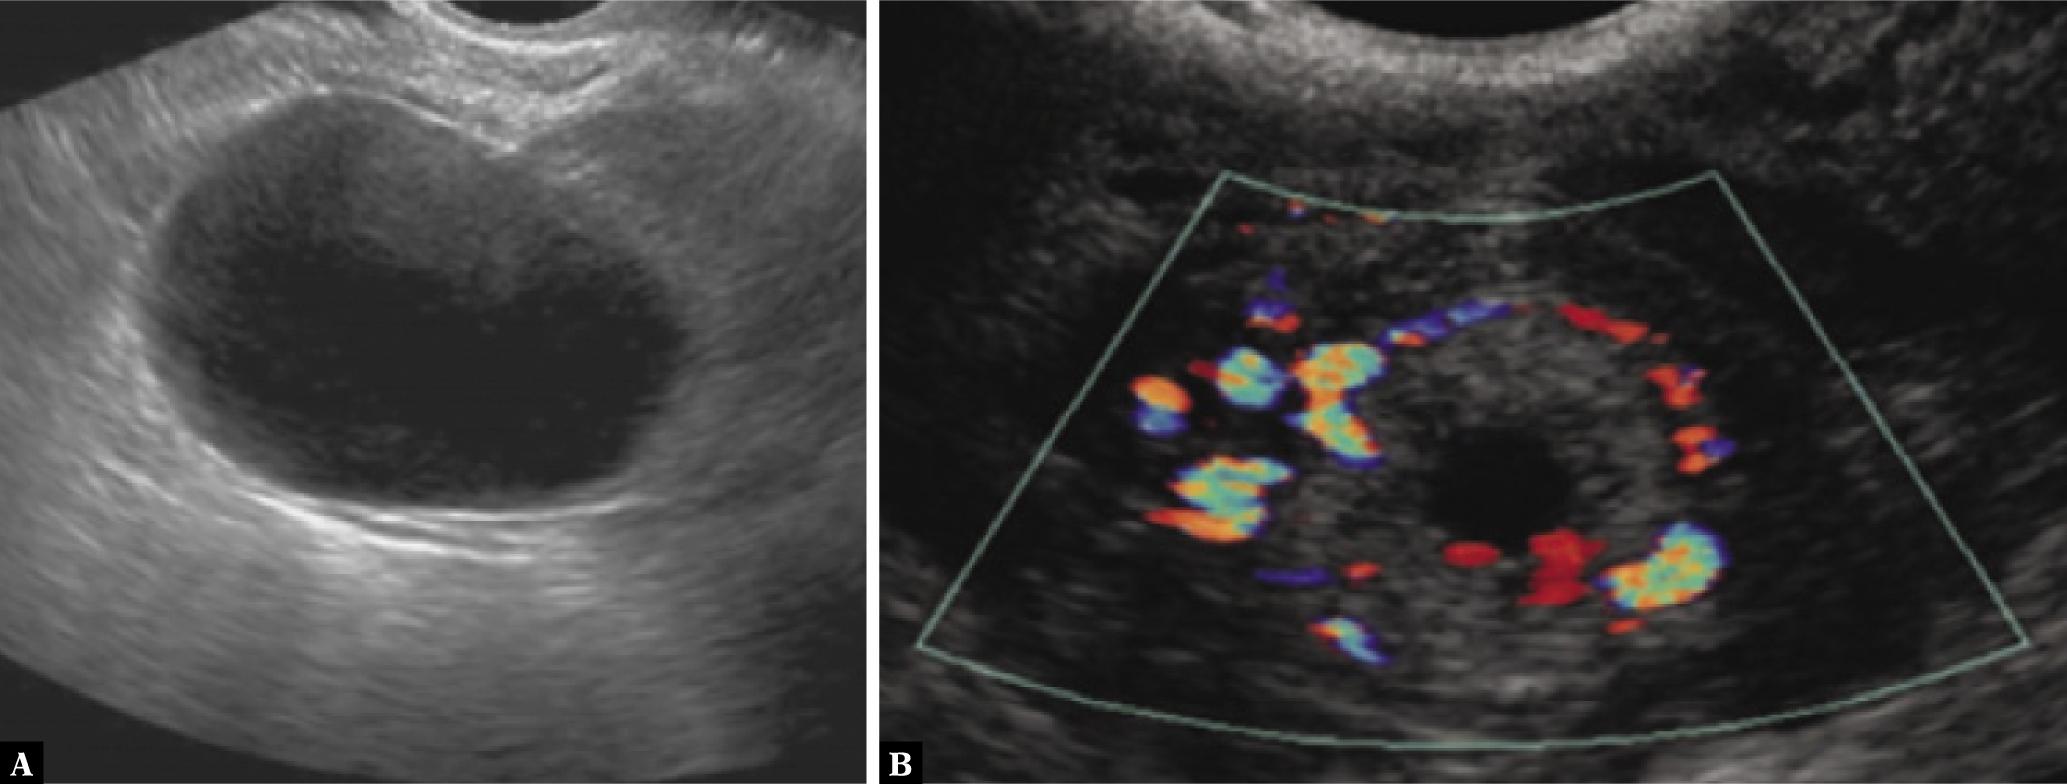

Fig. 5.